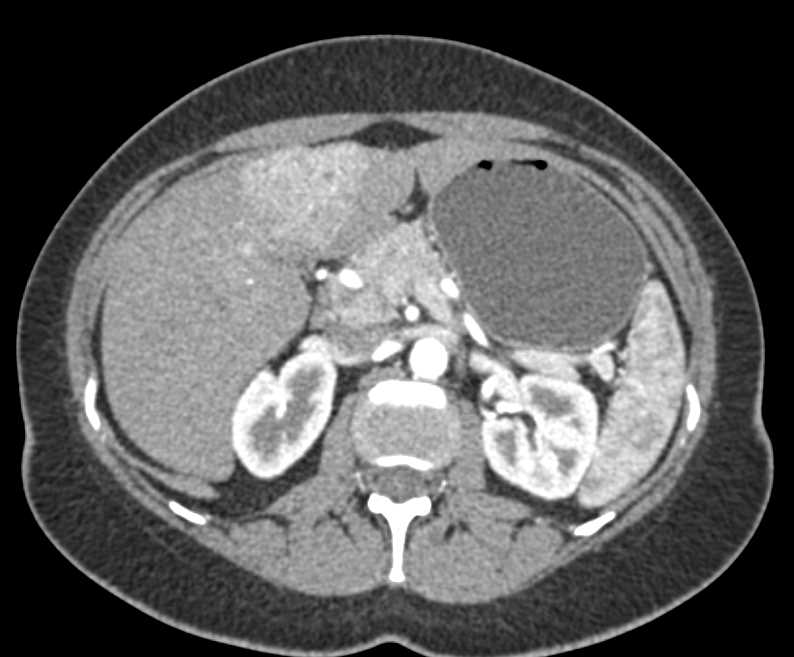

Focal Nodular Hyperplasia (FNH) Left Lobe Liver with Cinematic Rendering